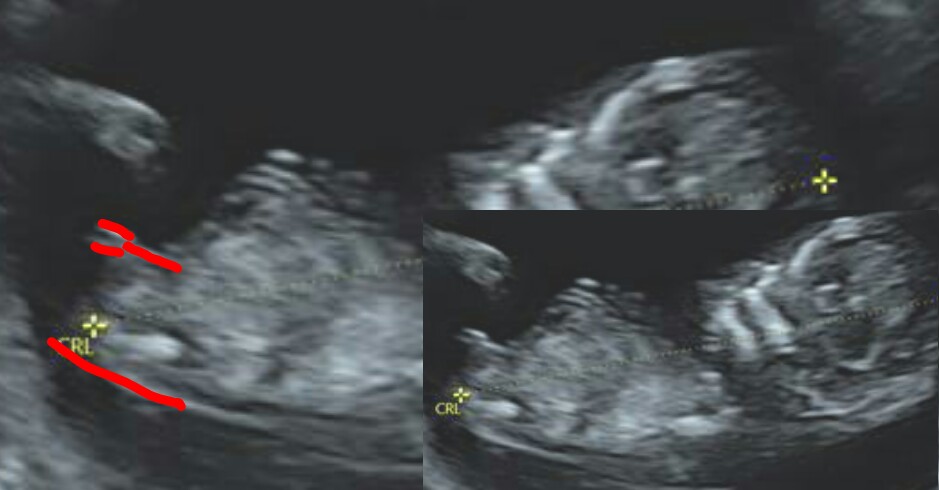

I did get some additional hope from IG. I was getting mostly boy guesses and the US forum leader said girl and posted her thoughts - see below.

Attachment 30115

I honestly think it's a girl nub. What I think is that your baby's bum is angled into the air, throwing the forked nub. I think that is making it look angled from far away by when you zoom in you can see the nub is in alignment with the spine. That forking is so much more common in girl nubs and to me it looks like forking rather than stacking. The pic is a little blurry and the graininess of it makes it look more like a stacked nub but I think it's a forked girl nub. The more I think about it, the more I think girl :-)

It is actually a very funny nub pic cos when I see it from far off I think classic boy but when you zoom in I think it's classic girl! I think it's the angle of the baby that is throwing us, if your baby's spine was flat and bum angled straight or down I think it would look much more obviously girly!

So I said I wasn't going to do this, but I totally played with the pic and adjusted the angle of the spine so more flat. I know, I know...I just can't help it lol!!! I'm trying not to obsess, but I also find it fun at least and keeps my hope alive!Attachment 30155